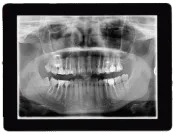

Digital X-Rays

Digital X-rays are an essential part of modern orthodontic care, offering greater accuracy, safety, and convenience. Unlike traditional X-rays, which rely on film and involve higher levels of radiation, digital X-rays use advanced technology to capture high-resolution images of your teeth and jaw with up to 90% less radiation exposure. These detailed images allow our orthodontists to diagnose issues like impacted teeth, jaw misalignments, and bone density problems early on, ensuring your treatment is both safe and effective.

At Davis & Goldberg Orthodontics, our digital X-ray system allows for quicker imaging and better-quality visuals, giving us an in-depth view of your oral health in real-time. This technology helps us plan precise treatments, whether you’re getting braces, Invisalign, or other orthodontic care. The digital format also enables immediate access to your X-rays, making it easy to share images with your dentist or specialists when needed, streamlining the entire treatment process. This focus on advanced technology ensures that you receive the highest standard of care with minimal radiation exposure and faster diagnostic results.